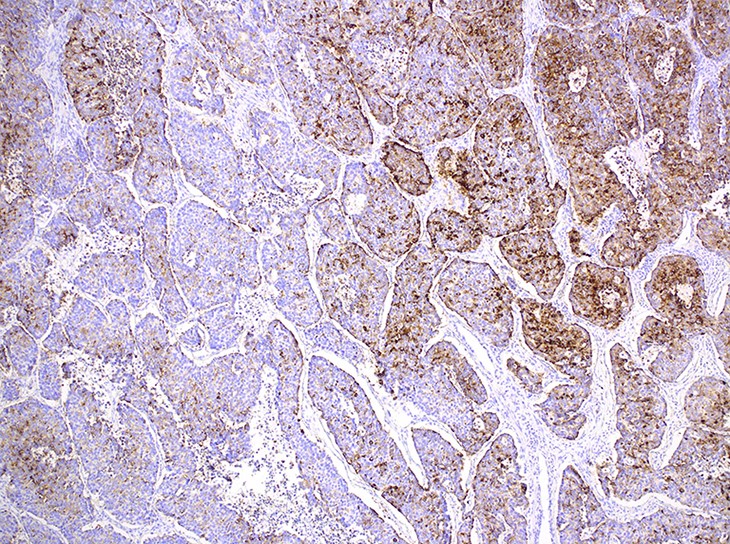

Microscopic (histologic) images

Contributed by Ioanna Abba Nteka, M.D., Aggeliki Cheva, M.D., Ph.D., Antonia Loukousia, M.D., Roseann Wu, M.D., M.P.H. and Kyriakos Chatzopoulos, M.D., Ph.D.

Positive stains

- Neuroendocrine markers, usually at least 2 focal to diffuse (chromogranin, synaptophysin, CD56), caution if CD56 is the only neuroendocrine marker expressed

A 76 year old man with a history of heavy smoking is diagnosed with a large pulmonary mass and undergoes lobectomy. The histologic features of the mass can be seen in the photograph above. Which initial panel of immunostains is more likely to be helpful in the differential diagnosis of this pulmonary malignancy from its most frequent counterparts?

C. ISNM1, p40 and napsin A. The differential diagnosis of this malignancy includes large cell neuroendocrine carcinoma, poorly differentiated adenocarcinoma and squamous cell carcinoma. In any case, additional immunostains will be needed to confirm the diagnosis.

Answer D is incorrect because although CD56 can be expressed in LCNEC, it should be used in caution when alone, as it is not as specific as other neuroendocrine markers. TTF1 can be expressed in half of LCNECs. Although p63 is a marker of squamous differentiation, it is not as specific as its p40 isoform. Answer B is incorrect because although LCNEC is likely to express all these 3 markers, the panel will not help rule out poorly differentiated adenocarcinoma. Answer A is incorrect because BRG1 expression is lost in undifferentiated SMARCA4 deficient thoracic tumors. INI1 can be partially lost in poorly differentiated non-small cell carcinomas with rhabdoid features or totally lost in SMARCB1 deficient carcinomas. NUT immunopositivity would raise the possibility of NUT carcinoma. None of these markers will be helpful in differentiating LCNEC from its more frequent mimics. Answer C is correct because ISNM1 is a highly sensitive and specific marker of neuroendocrine differentiation . Similarly, p40 isoform of p63 is highly specific for squamous differentiation. Napsin A is most frequently expressed in lung adenocarcinomas. This panel of immunostains will be the most helpful, since ISNM1 positivity will point towards the diagnosis of LCNEC, while p40 and napsin A negativity will make the possibilities of squamous cell carcinoma and adenocarcinoma remote.